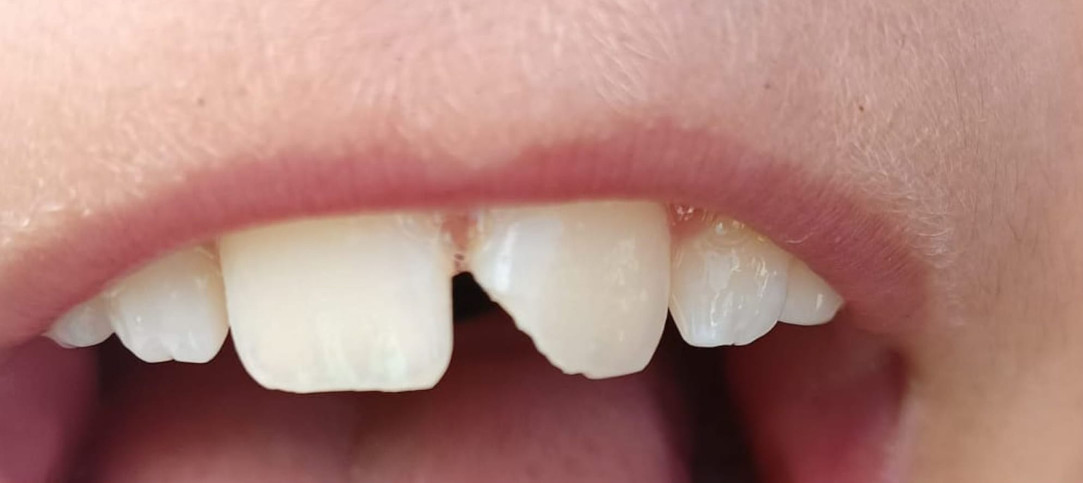

Caso Clinico

Restauri in composito

Il restauro di un dente cariato o fratturato si ottiene con il composito. È un materiale, in uso

da circa 45 anni, che diviene tutt’uno col dente.

È innocuo al dente e all’organismo. La gran parte dei restauri ha già superato i 35 anni.

Prima

Dopo